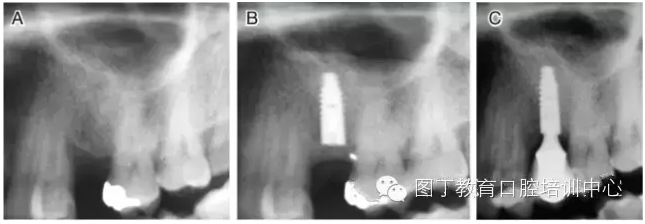

臨床上,可使用曲面體層放射線法及CT掃描方法對上額竇及可用骨量進行評估。其中曲面體層放射線法可提供多數(shù)病例的硬腭致密影像,為治療計劃提供有價值的參考(圖1);而使用CT掃描可提供骨密度信息。如骨高度、密度、牙槽嵴的方向位置,皮質(zhì)骨和松質(zhì)骨的特點,上頜竇黏膜厚度,病理狀態(tài)等。顯然,在上頜竇底提升術(shù)中,CT掃描影像的信息對于手術(shù)設(shè)計和減少治療風(fēng)險非常重要。

圖1 采用曲面體層放射線法評估